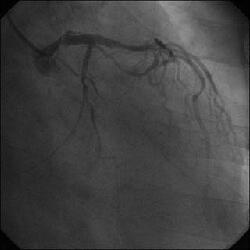

�Ǘ��72�Ώ����Brisk factor��HT, HL, DM�ł��B

��2�T�ԑO�̔��ǂƎv����Recent MI�ł��BLAD#7: total��Tristar3.0�~18?�����

�܂����B

����LCx ostium: 75%�ł��B������PCI���悤�Ǝv���̂ł����A�ǂ̂悤��strategy

���l������ł��傤���H

���Ȃ݂ɓ��@�ł�DCA�g�p�o���҂͂��܂���B

DCA�ł���l��A��Ă���A�Ƃ����I�������܂߂Č䏕��������K���ł��B